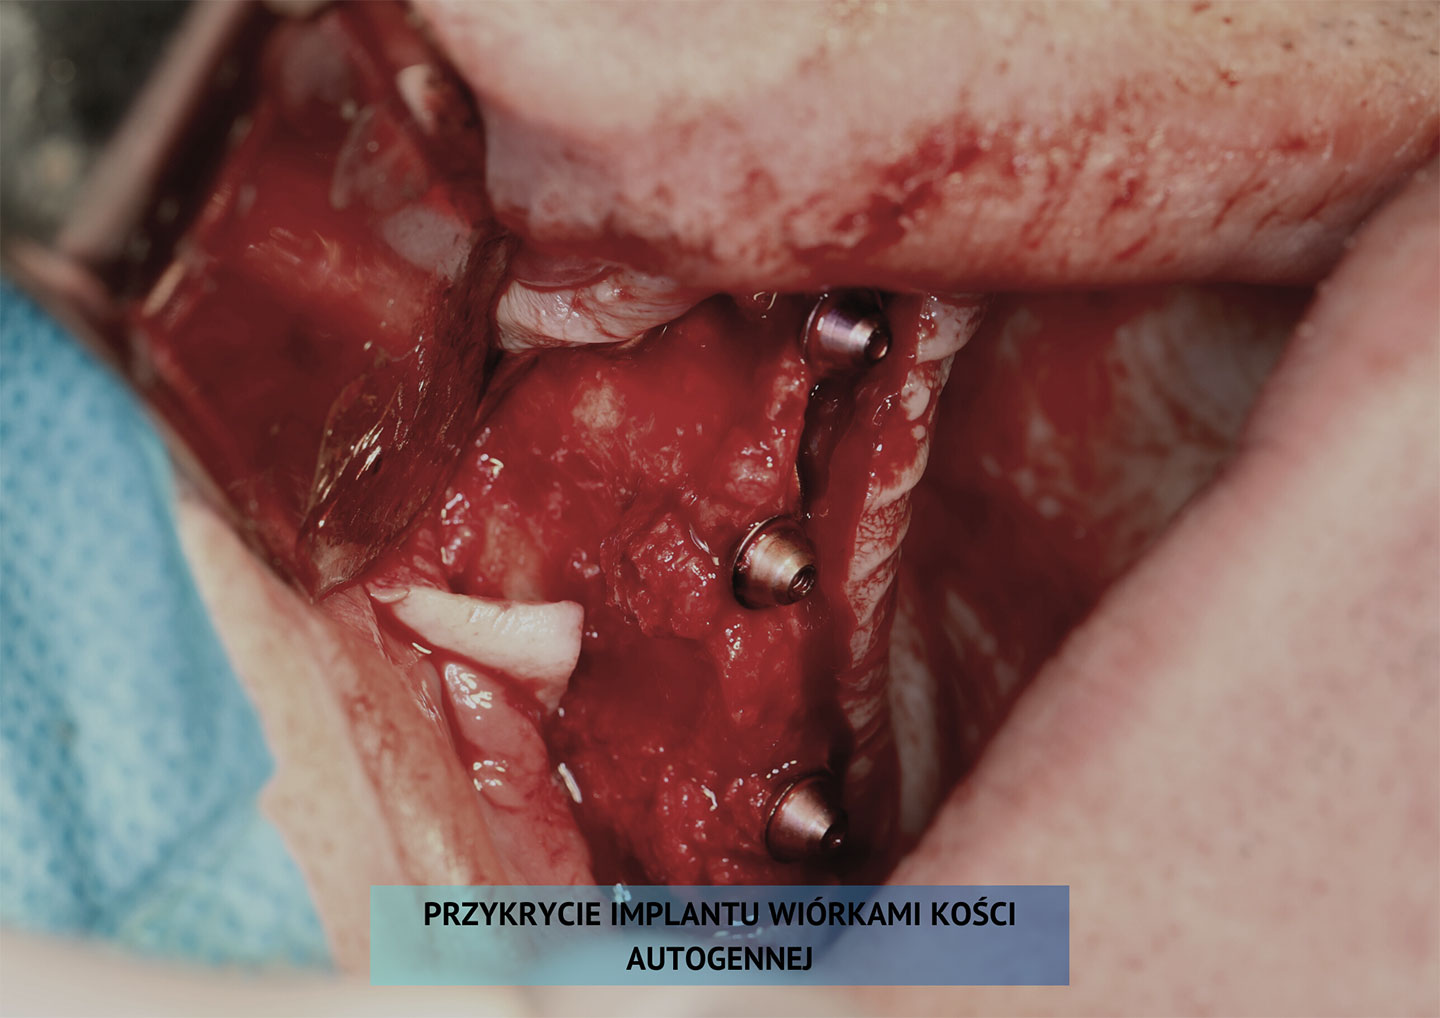

5. Etapy wszczepienia implantów

Zabieg wszczepienia implantu podokostnowego u pacjenta z całkowitym bezzębiem szczęki w znieczuleniu miejscowym.